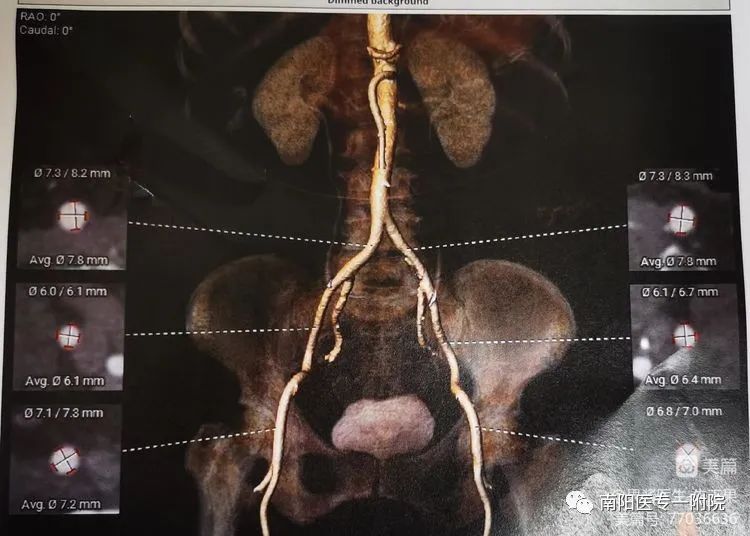

术前评估流程